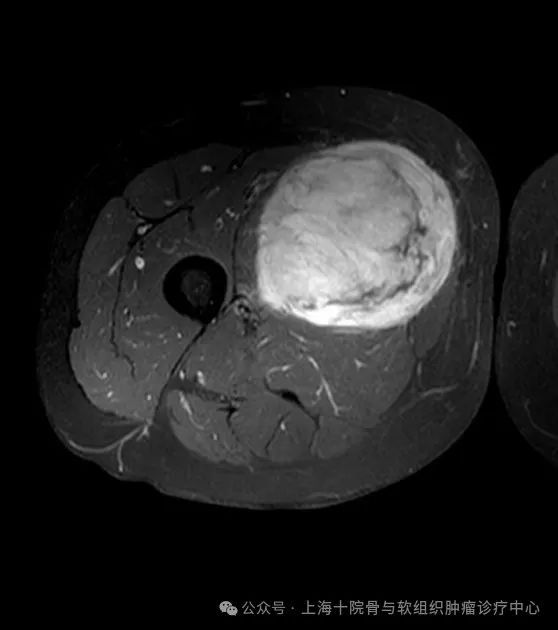

什么是未分化多形性肉瘤未分化多形性肉瘤(UndifferentiatedPleomorphicSarcoma,UPS),以前称为恶性纤维组织细胞瘤(MalignantFibrousHistiocytoma,MFH),是一种罕见且具有高度侵袭性的软组织肉瘤。它主要发生在成年人,特别是老年人中。大腿是UPS的好发部位。未分化多形性肉瘤是什么症状,怎么发现的?未分化多形性肉瘤的临床表现多种多样,主要包括以下几个方面:1.肿块:大多数患者会发现一个无痛的、逐渐增大的肿块,通常位于四肢、躯干或腹部。2.疼痛:虽然肿块通常无痛,但在某些情况下,尤其是当肿瘤压迫神经或其他结构时,患者可能会感到疼痛。3.功能障碍:如果肿瘤位于四肢,可能会引起运动功能障碍或肢体无力。4.全身症状:在晚期,患者可能会出现全身症状,如体重减轻、疲劳和发热。怎么确诊未分化多形性肉瘤呢?根据NCCN软组织肉瘤指南,未分化多形性肉瘤的诊断主要依赖于影像学检查(如MRI和CT)和组织病理学检查。影像学检查有助于确定肿瘤的位置、大小和侵袭性,而组织病理学检查则通过活检样本的显微镜分析来确认诊断。HE染色下的UPS形态。为什么会得未分化多形性肉瘤呢,有什么原因吗?未分化多形性肉瘤的确切病因尚不明确,但研究表明,以下几个因素可能与其发病有关:1.基因突变:一些未分化多形性肉瘤患者体内存在特定的基因突变,如TP53、RB1和MDM2基因的突变。2.辐射暴露:长期暴露于放射线下可能增加未分化多形性肉瘤的风险。这在接受过放射治疗的癌症患者中尤为明显。3.免疫抑制:免疫系统功能低下的患者(如艾滋病患者或接受免疫抑制治疗的器官移植患者)也有较高的发病风险。4.其他因素:一些环境和职业暴露,如接触某些化学物质,也可能增加风险。未分化多形性肉瘤能治好吗,该怎么治?未分化多形性肉瘤的治疗通常包括手术、放疗和化疗。根据NCCN和中国肉瘤指南,具体的治疗方案应根据患者的个体情况制定。1.手术:手术是未分化多形性肉瘤的主要治疗方法。目标是彻底切除肿瘤,并尽可能保留正常组织。对于较小的肿瘤,通常可以通过局部切除实现治愈;对于较大的或侵袭性的肿瘤,可能需要更广泛切除,甚至截肢。2.放疗:放疗通常用于术后辅助治疗,以减少局部复发的风险。在某些情况下,放疗也可作为主要治疗手段,特别是对于无法手术切除的肿瘤。3.化疗:化疗在未分化多形性肉瘤的治疗中作用有限,但对于某些高风险患者或晚期病例,化疗仍可作为辅助治疗手段。常用的化疗药物包括阿霉素(doxorubicin)和异环磷酰胺(ifosfamide)。未分化多形性肉瘤有什么新药新进展吗?近年来,未分化多形性肉瘤的研究取得了一些重要进展,主要集中在以下几个方面:1.靶向治疗:培唑帕尼、瑞戈非尼等靶向药物2.免疫治疗:免疫检查点抑制剂(帕博利珠单抗、纳武单抗等)在一些早期临床试验显示,可能对部分未分化多形性肉瘤患者有效。3.分子诊断:新一代测序技术的应用使得对未分化多形性肉瘤的基因组学研究成为可能。这不仅有助于揭示其发病机制,还可以为个体化治疗提供依据。肉瘤的免疫治疗正方兴未艾。更多关于未分化多形性肉瘤的问题,请至上海市第十人民医院就诊咨询。骨科张春林主任专家门诊(每周一下午,门诊5105诊室),张春林主任特需门诊(每周四上午,门诊5408诊室)骨科吴卫平主任专家门诊(每周三上午,门诊5114诊室)。《骨肿瘤骨病》专科门诊,每周一、三、五上午,门诊楼2楼2110诊室。《体表肿物、骨与软组织肿瘤》专病门诊,每周一、三、五上午,门诊楼2楼2110诊室。